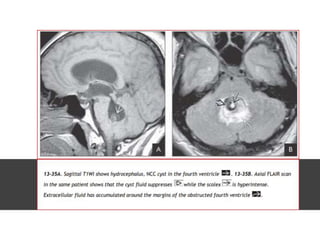

Neurocysticercosis

Cysticercosis is the most common parasitic infection in the world, and

CNS lesions eventually develop in 60-90% of patients with

cysticercosis.

LOCATION

• T. solium larvae are most common in

the CNS, eyes, muscles, and

subcutaneous tissue. The intracranial

subarachnoid spaces are the most

common CNS site, followed by the

brain parenchyma and ventricles

(fourth > third > lateral ventricles)